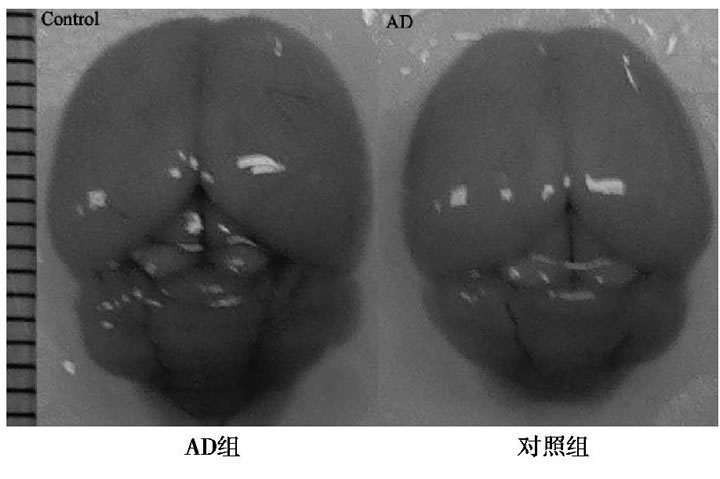

與對照組比較, AD小鼠完整腦組織表面泛白、無血色, 血管明顯減少, 表明D-半乳糖聯合三氯化鋁已經對小鼠的腦組織形成退行性損傷。見圖1。

圖1 AD組和對照組小鼠全腦圖